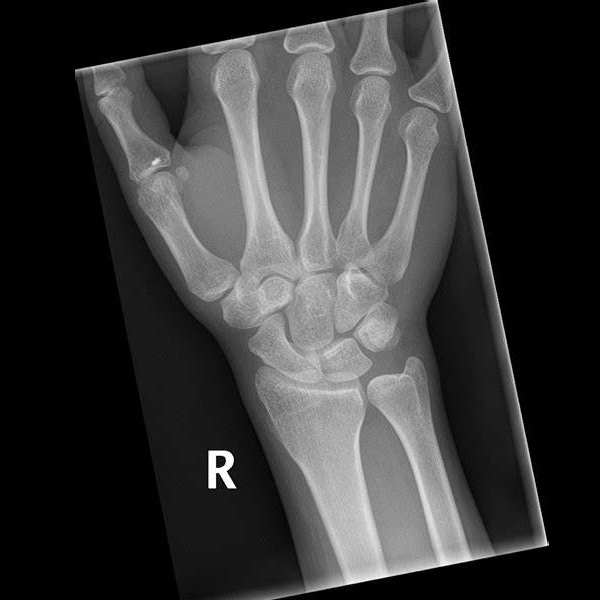

Learn the bony anatomy then test yourself